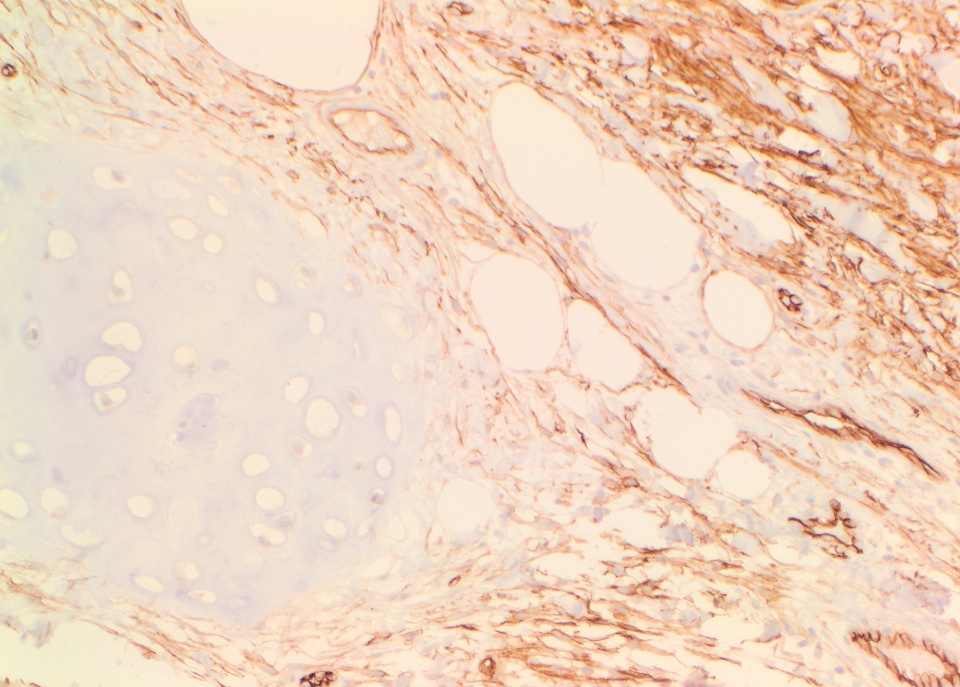

The tumor cells were strongly positive for CD34, ER and PR.

The conventional histologic appearance is of bland fibroblast-like spindle cells with relatively short, stubby nuclei. The cells are interspersed between collagen bundles and a variable amount of adipose tissue. The stroma can show hyalinization and / or myxoid change. Mast cells may be conspicuous (Goldblum: Enzinger and Weiss's Soft Tissue Tumors, 6th ed, 2013, Am J Surg Pathol 2016;40:361). Several different variants of MTMF have been described: cellular, infiltrating, collagenized / fibrous, lipomatous, myxoid, epithelioid and deciduoid-like. Areas of smooth muscle, bone and cartilage can be seen (Am J Surg Pathol 2009;33:1085). Rare tumors may show a neurilemmoma-like pattern. "Symplastic" or degenerative cytologic atypia - enlarged, hyperchromatic, multinucleated cells - can be present (Am J Surg Pathol 2016;40:361).

The tumor cells were strongly positive for CD34, ER and PR.

The conventional histologic appearance is of bland fibroblast-like spindle cells with relatively short, stubby nuclei. The cells are interspersed between collagen bundles and a variable amount of adipose tissue. The stroma can show hyalinization and / or myxoid change. Mast cells may be conspicuous (Goldblum: Enzinger and Weiss's Soft Tissue Tumors, 6th ed, 2013, Am J Surg Pathol 2016;40:361). Several different variants of MTMF have been described: cellular, infiltrating, collagenized / fibrous, lipomatous, myxoid, epithelioid and deciduoid-like. Areas of smooth muscle, bone and cartilage can be seen (Am J Surg Pathol 2009;33:1085). Rare tumors may show a neurilemmoma-like pattern. "Symplastic" or degenerative cytologic atypia - enlarged, hyperchromatic, multinucleated cells - can be present (Am J Surg Pathol 2016;40:361).